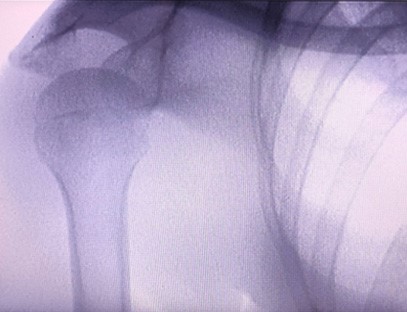

Vår ortopedisk röntgenmaskin är en högkvalitativ produkt som designades speciellt för ortopedisk bildbehandling. Den kan användas för diagnos och behandlingsplanering av olika ortopediska tillstånd, inklusive frakturer, dislokationer, artrit och bentumörer. Den är utrustad med avancerad röntgenteknik som möjliggör högkvalitativa bilder med reducerad strålningsexponering. Maskinen har ett högupplöst bildsystem och kan ta bilder av vilken benstruktur som helst med stor tydlighet.

Vår ortopediska röntgenmaskin kan användas inom olika medicinska specialiteter, inklusive ortopedi, neurologi och akutmedicin. Det används ofta för fluoroskopisk observation av mänskliga lemben, veterinär- och djursjukhus, behandling av sårade på sportplatser, byggnader, oceangående fartyg, avlägsna områden och militärfältsplatser. Några av de kliniska tillämpningarna inkluderar:

1. Diagnos av frakturer, dislokationer och andra benskador.